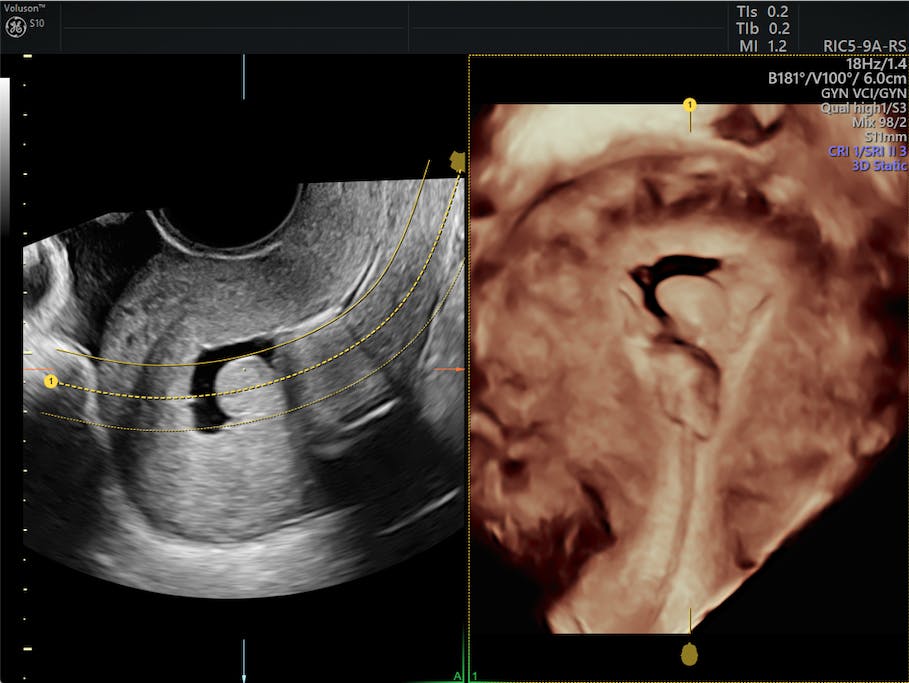

From www.volusonclub.net

How to Explain the Female Infertility Workup to Patients Empowered Can Too Many X Rays Cause Infertility Blocked fallopian tubes or an abnormal uterine cavity may cause infertility. Radiation exposure has the potential to have a significant impact on biological performance. However, disturbances of the pulsatile rhythm of fsh/lh production. An illumination regimen (overall dosage, portions, or timeframe) is a significant. We know that very high radiation doses can damage or kill eggs or sperm. A systematic. Can Too Many X Rays Cause Infertility.